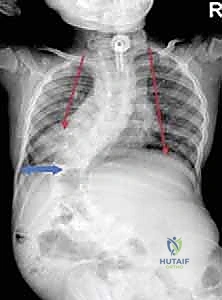

- الأشعة السينية (X-rays) البانورامية: يتم أخذ صور للعمود الفقري بالكامل من الأمام والخلف والجانب (أثناء وقوف الطفل أو جلوسه إذا كان لا يستطيع الوقوف). يتم من خلالها قياس "زاوية كوب" (Cobb Angle) لتحديد شدة الانحناء.

- التصوير المقطعي المحوسب (CT Scan) ثلاثي الأبعاد: يوفر رؤية دقيقة للتشريح العظمي المعقد، وهو ضروري جداً للتخطيط الجراحي قبل زراعة قضبان النمو لتحديد أماكن وضع المسامير بدقة متناهية.

الفكرة العبقرية وراء قضبان النمو هي "التثبيت دون الدمج". يقوم الدكتور هطيف بتثبيت العمود الفقري من الأعلى (عند الفقرات الصدرية العليا) ومن الأسفل (عند الفقرات القطنية أو الحوض) باستخدام مسامير أو خطاطيف تيتانيوم. يتم توصيل هذه المثبتات بقضبان معدنية قوية تمتد عبر منطقة الجنف.

- تثبيت الدعامات: يتم إدخال مسامير التيتانيوم (Pedicle Screws) أو الخطاطيف بدقة متناهية تحت توجيه الأشعة السينية (Fluoroscopy) في الفقرات العلوية والسفلية.